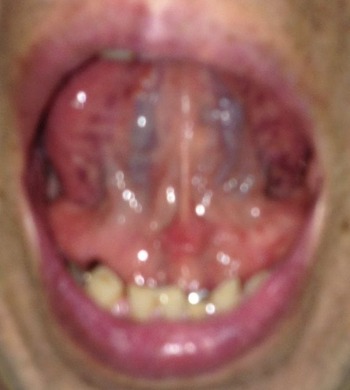

¡Ú2013ǯ6·î14Æü¡¦´ÁÊýÌôÉþÍÑÁ°¤ÎÀå¤Îɽ¡Û

ÀåÁ餻¤ÆÇö¤¤¡¡

µµÎö¤¬½Ä¤ËÂô»³¿¼¤¯Æþ¤ê

·ì¤äµ¤¤¬ÄűդÎÉÔ¤Ǥ¹

Èó¾ï¤ËÂΤ¬¼åÂ⽤ÎÀå¤Ç¤¹

¡Ú2013ǯ7·î17Æü¡¦´ÁÊýÌôÉþÍÑ35Æü¸å¤ÎÀå¤Îɽ¡Û

¡Ú2013ǯ10·î14Æü¡¦´ÁÊýÌôÉþÍÑ92Æü¸å¤ÎÀå¤Îɽ¡Û

¡Ú2013ǯ6·î14Æü¡¦´ÁÊýÌôÉþÍÑÁ°¤ÎÀå¤Î΢¡Û

ÀÅÌ®·ì´É¤¬¹õ¡¹´â¤ä½ÐÍèʪ¤Î¤¢¤ëÊý¤Ï

¹õ¡¹¤ÎÀÅÌ®·ì´É¤¬¤¢¤ê¤Þ¤¹¡£

·ò¹¯¤ÊÊý¤Ë¤Ï¹õ¤Î¿§¤Ï¤¢¤ê¤Þ¤»¤ó¡£

¡Ú2013ǯ7·î17Æü¡¦´ÁÊýÌôÉþÍÑ35Æü¸å¤ÎÀå¤Î΢¡Û

¡Ú2013ǯ10·î14Æü¡¦´ÁÊýÌôÉþÍÑ92Æü¸å¤ÎÀå¤Î΢¡Û